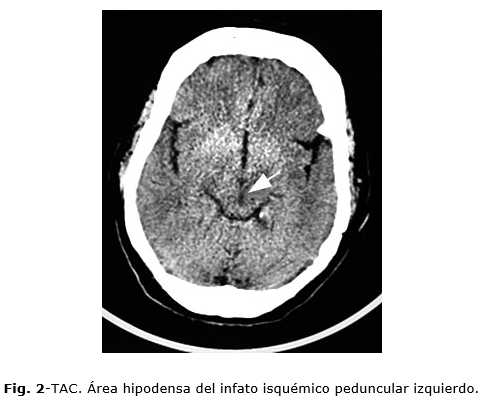

A las 48 h se mantiene estable con tratamiento médico, TAC multicorte de cráneo simple: Lesión hipodensa isquémica izquierda por debajo de la proyección del tálamo que toma la región del pedúnculo cerebral del mismo lado (mesencéfalo) reciente. (Figuras 1 y 2 cortes coronales, Fig. 3 sagital)

Diagnósticos: Infarto cerebral aterotrombótico peduncular izquierdo con hemiplejia alterna de Weber. Diabetes tipo 2 con mal control metabólico. Hiperlipidemia mixta. Cardiopatía isquémica arterioesclerótica. Hipertensión arterial controlada. Estenosis valvular aórtica de etiología fibro-esclero-degenerativa. Anciana frágil.